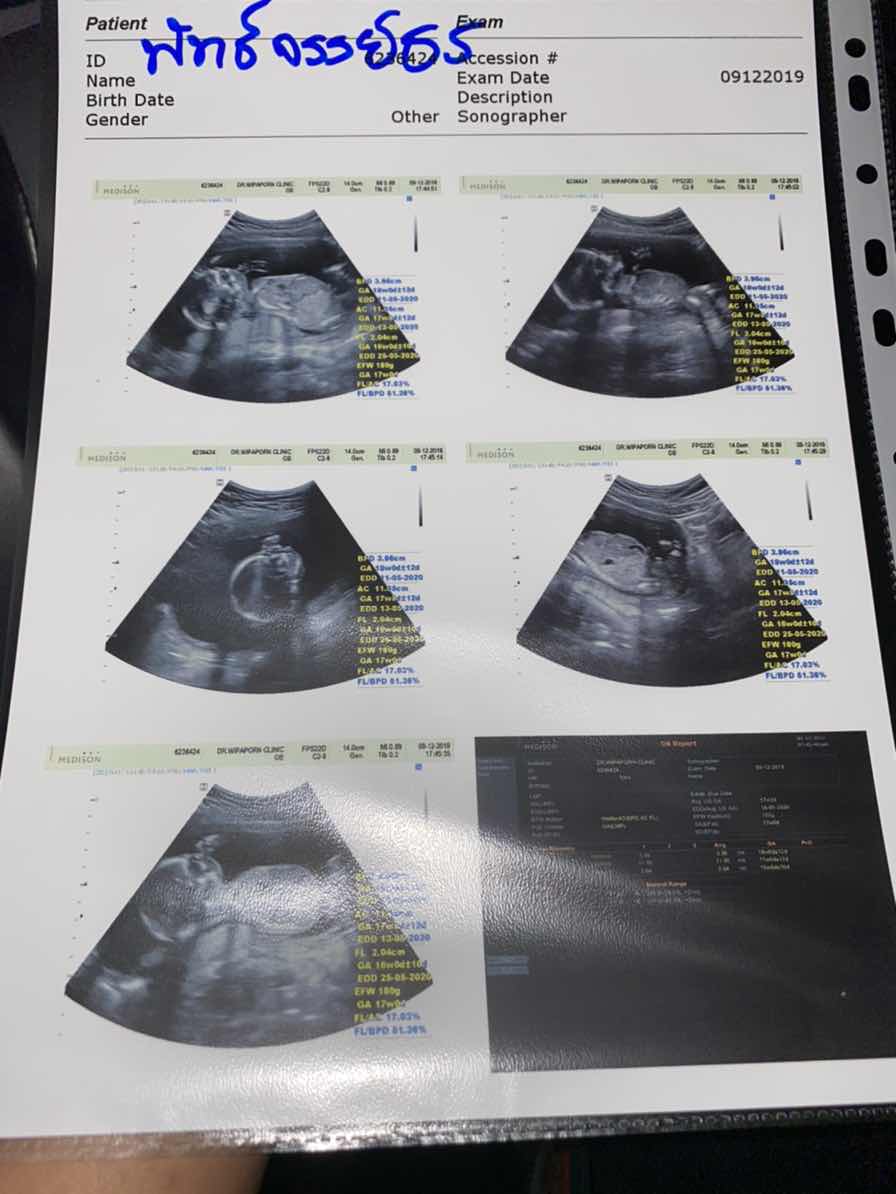

พึ่งซาวด์วันนี้ค่ะ อยากได้ผช. ได้สมใจ ?❤️?